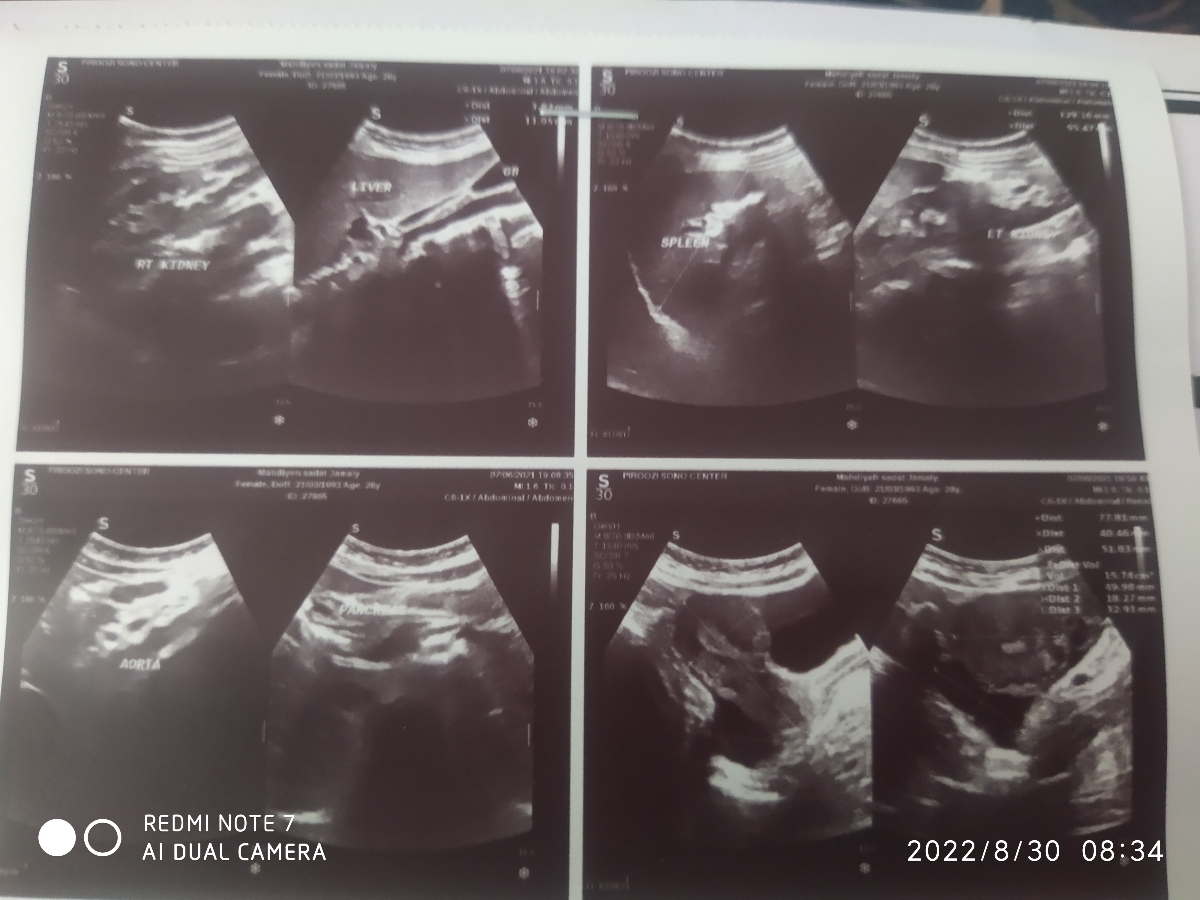

سلام دکتر جون دکتر سونو گفت در لگنم ۱۵ سیسی مایع جمع شده . علت چی میتونه باشه؟؟؟؟

البته دکتر اول گفت احتمالا حاملگی خارج رحمت با کیست پاره شده یا عفونته و باید اورژانسی سونو واژینال بشی و چون سونو شکمی هم داشتم برای سونوی کلیه ها به پهلو میشدمبعد از اتمام کار دوباره مایع کلدوساک خلفی را چک کرد گفت اااا چرا کم شد و برای همین در برگه جواب نوشته مختصر مایع دیده شده . حالا باید نگران باشم یا خیر

عزیزم سونوگرافی را ارسال کنید تا ببینم

دکتر جون آیا این تیتر بتا هست یا بتا معمولی چون سونوگرافیست تاکید داشت تیتر بتا داده باشم .چون میخواست بدونه مشکوک به بارداری هستم یا نه

چون اول به دستیارش گفت بنویسه که دوباره تیتر بتا تکرار شود و سونو واژینال اورژانسی انجام شود . ولی وقتی پهلو به پهلو شدم و دید مایع کمتر شده گفت دردت الان تمام شده گفتم نه گفت چیزی ازت بیرون نیامده گفتم نه گفت شاید حرکت کردید مایع حرکت کرده و چون شک داشت به دستیارش گفت متن رو پاک کنه و بنویسه مختصر مایع دیده شده. ولی به من گفت فردا حتما برم دکتر تا برسسی کنم و گفت فردا حتما از دکتر بخواه سونو واژینال انجام بده. ولی امروز دکترم نیست😢

جان دلم این بتای معمولی است و اگر یادت باشد من هم تاکید داشتم اگر تیتر بتا انجام شده قابل اعتماد است، مجددا آزمایش را به شیوه تیتر در یک آزمایشگاه معتبر تکرار کنید و نتیجه را گزارش دهید

عزیزم طبق گزارش آزمایشگاه که اینطور بنظر میرسد چون اگر تیتر بود باید کنار بتا نوشته میشد